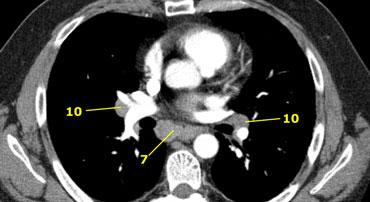

Hạch rốn phổi, thùy phổi và (phân) phân thùy nhóm 10-14

Tất cả các hạch này đều thuộc nhóm N1.

10. Hạch rốn phổi

Bao gồm các hạch tiếp giáp với phế quản gốc và các mạch máu rốn phổi.

Bên phải, trải dài từ bờ dưới tĩnh mạch đơn đến vùng gian thùy.

Bên trái, từ bờ trên động mạch phổi đến vùng gian thùy.

Hạch rốn phổi là các hạch thùy gần, nằm ở phía xa so với nếp gấp màng phổi trung thất và các hạch kề phế quản trung gian bên phải.

Các hạch từ nhóm 10 đến 14 đều là hạch N1, vì chúng không nằm trong trung thất.